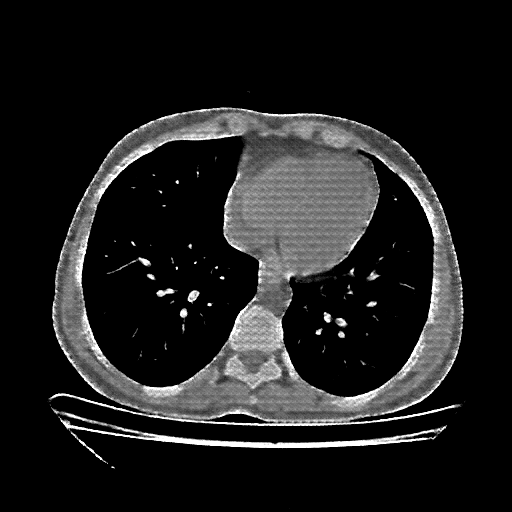

Targeted Slice 70 - Network-Normalized Analysis (Generated vs Real Venous)

0.727

SSIM Score

0.171

RMSE

0.130

MAE

Average Network-Normalized Metrics Across All Slices (112 slices) - Generated vs Real Venous

0.778

SSIM Score (Avg)

0.143

RMSE (Avg)

0.101

MAE (Avg)

Reconstructed NATIVE CT scan (cycle consistency)

No window - Raw intensity values